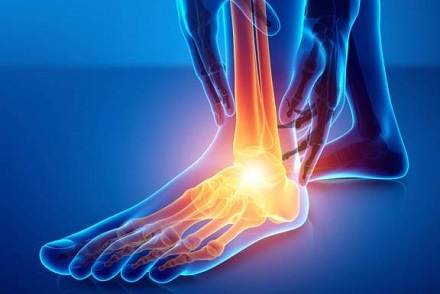

Inflammation and degeneration of the achilles tendon in the lower calf or back of the heel

Causes: Repetitive stress through the tendon, bone spurs, muscle imbalance

Symptoms: Pain, worse in the morning, thickened lump in tendon, stiffness

Full Article: Achilles Tendonitis